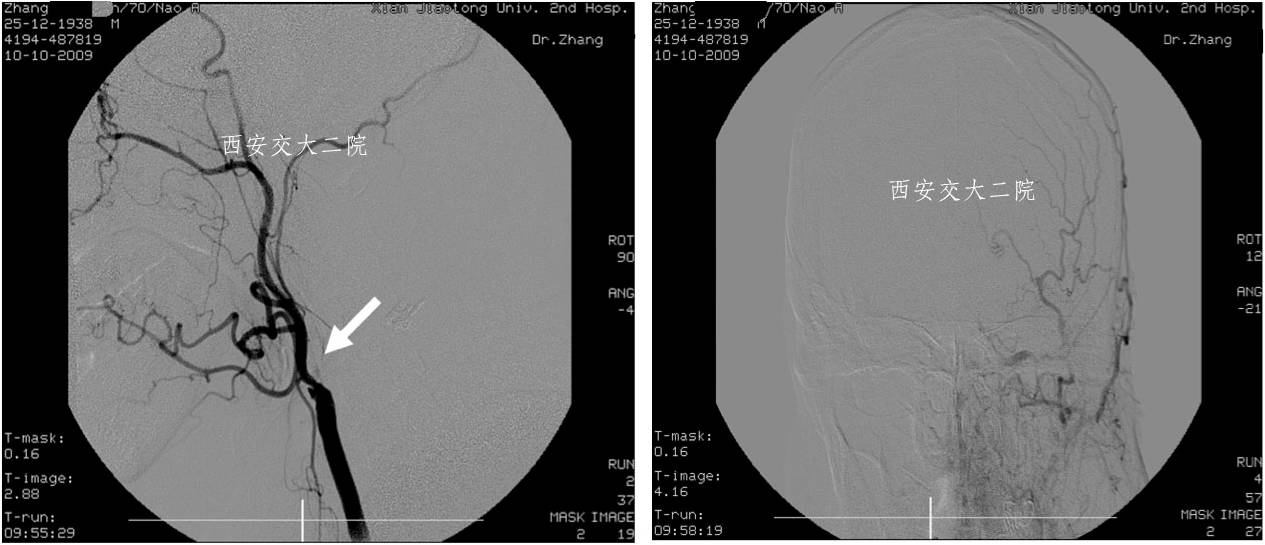

Case 1 颈内动脉C1段急性闭塞(2009年)

》男,70岁,突发右侧肢体无力3小时,DSA提示左侧颈内动脉起始段闭塞。

Case 2 左侧大脑中动脉溶栓+支架 (2009年)

》男,44岁,突发言语不能,右侧肢体活动不灵2小时。

》尿激酶10万后MCA未通,给予Apollo支架植入。